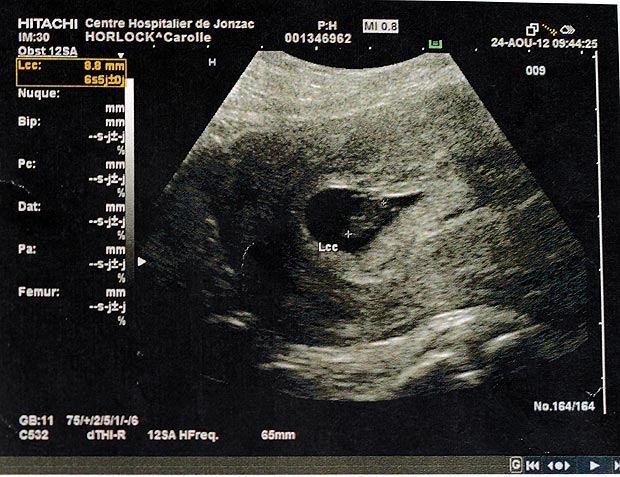

英國赫特福德郡一名號稱全球最多產的超級代母,先後為九對不育夫婦代生嬰兒,更曾誕下雙胞胎、三胞胎。隨年紀漸大,高齡懷孕 風險高,超級代母明年四月誕下第十三胎後封肚。

四十六歲的單親媽媽超級代母霍洛(Carole Horlock),多年前誕下兩名女兒後,體會到為人母的喜悅。超級 代母自言享受懷孕的過程,分別為不同國家的不育夫婦產子,更曾順利讓兩女一男的三胞胎呱呱落地。